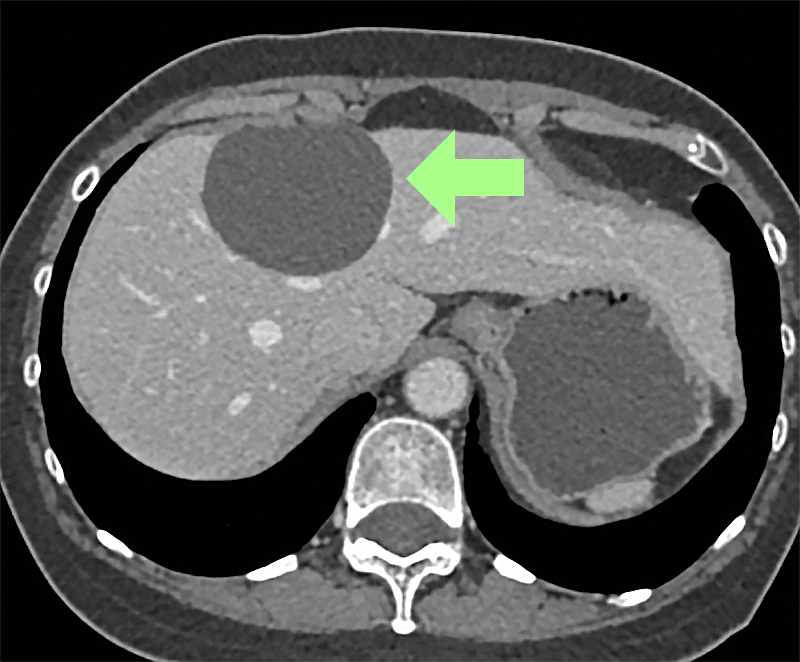

Liver cysts

An estimated five percent of the population develop liver cysts. They are benign growths that contain fluid produced by the cell wall of the cyst. Most cysts do not need therapy, but some can grow and be large enough to cause pain. These can be drained laparoscopically as an outpatient procedure to alleviate symptoms.

Diagnosing liver cancer or metastatic liver cancer may include one more tests. They include blood tests and imaging tests, such as a CT scan, ultrasound, and MRI. It is sometimes necessary to remove a sample of liver tissue for biopsy.

- Computed tomography scan (CT or CAT scan)

- Magnetic Resonance Imaging (MRI)